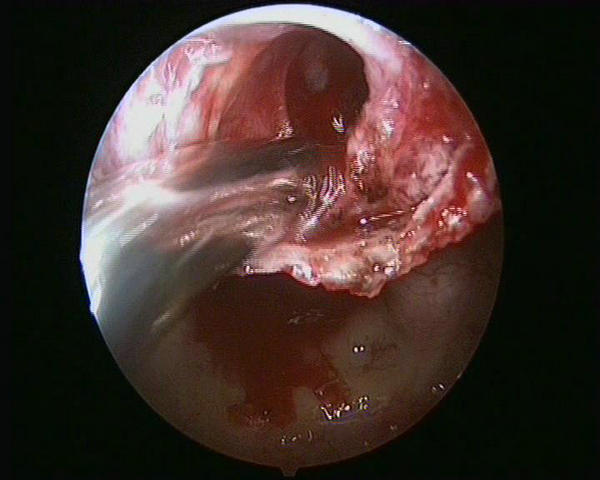

经神经外科专家组分析讨论病例,付旭东副主任决定采用创伤小、出血少的神经内镜技术切除肿瘤。这是神经外科的一项新微创技术。手术当日,在麻醉科、手术部的大力配合下,由神经外科一病区付旭东副主任操刀,由患者鼻孔插入直径仅4毫米的高清神经内镜,直视下避免颈内动脉、视神经、垂体柄等重要结构的损伤。经过2个多小时的细致暴露、分离和切除,顺利地全切了肿瘤,整个手术过程清晰地显示在巨大的高清电视屏幕上,流畅而精彩(图2、3、4)。

图2

图3

图4